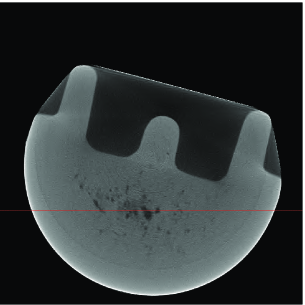

Industrial object reconstruction. We apply our proposed methods to reconstruct an industrial object from real fan-beam X-ray CT projections. First, we performed the standard fan-to-parallel beam conversion (see [7, Sec. 3.4]) and generated parallel-beam projections with spacing and measurement array size of elements, yielding frequency-domain measurements per projection. Our full mask has circular shape containing signal elements. The outer-shell mask containing pixels has been constructed from the phantom’s parallel-beam sinogram using , see Section V.

We compare the reconstruction performances of mask DORE () and DORE () with ; the mask FPC and FPC schemes using the regularization parameter ; the standard FBP method. The reconstructions of mask FPC and FPC are very similar to those of mask DORE and DORE; hence we present only the mask DORE and DORE reconstructions in this example. Figs. 3–3 show the reconstructions of the FBP, DORE, and mask DORE methods from projections whereas Figs. 3–3 show the corresponding reconstructions from limited-angle projections. Figs. 3–3 show the corresponding reconstruction profiles for slices depicted in Figs. 3–3. Observe the aliasing correction and denoising achieved by the sparse reconstruction methods.